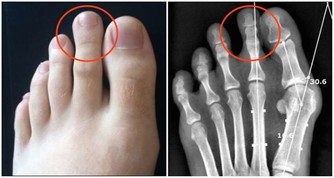

沒有了運動的支持,下肢的血液循環變慢,就容易讓血管變得擁堵。在臨床上也發現,靜脈曲張、下肢血栓的人,最好不要久坐、久站,更不要久躺,久躺在這3個方式當中,算是可以讓機體消耗熱量非常低的了,只會讓人越變越懶。

如果是比較嚴重的情況,還容易讓血管的血液流通變慢,增加血栓的發生危險。